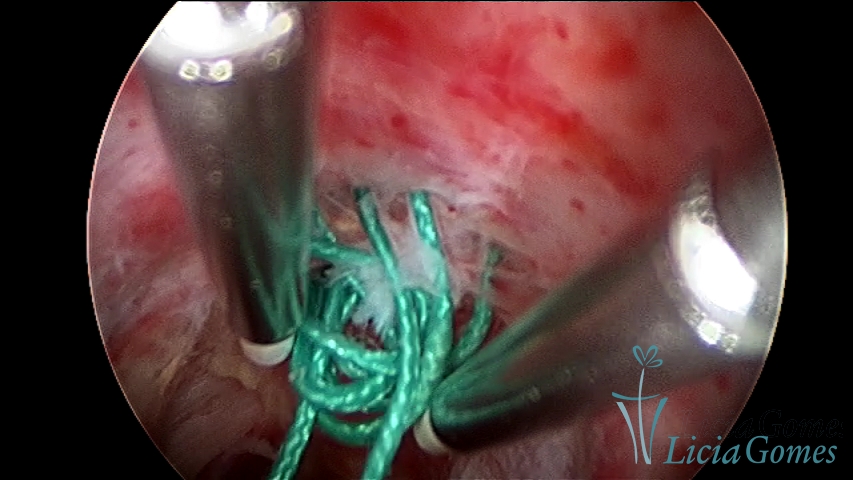

Retração da cicatriz de cesárea com fio não absorvível há 30 anos ressecção com enegia bipolar